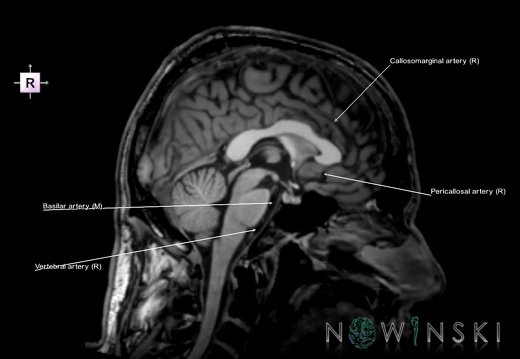

G6.T15.2.V2.P10.Intracranial arteries–Triplanar

G6.T15.2.V2.P10S.Intracranial arteries–Triplanar